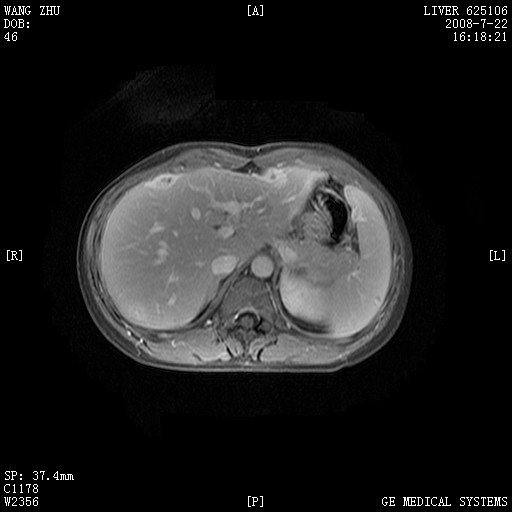

图像有点乱,病灶边缘清楚,可见纤维囊壁,灶旁可见异常灌注,增强显著增强,病灶有早期完全充填,无快退征像,考虑炎性病灶,肝结核可能性大,不知有何病史

肝前外缘见一类圆形囊性病灶,边缘强化,灶周肝为炎性渗出改变,其肝周可见少量腹水,符合炎性病变,病史较长---考虑腹膜结核。肝为外压性改变,脾为动脉期改变。